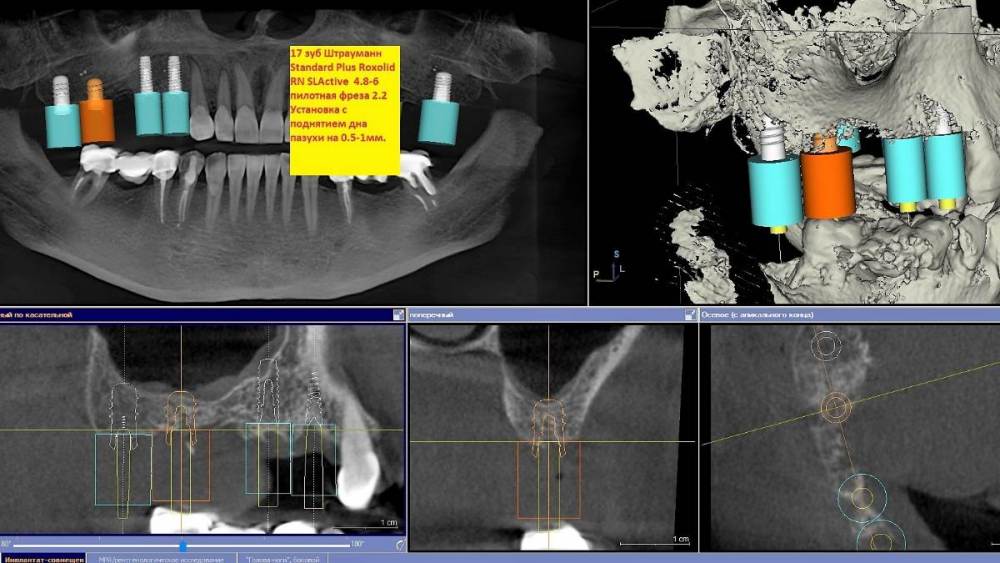

Ponchik Опубликовано 12 сентября, 2021 Поделиться Опубликовано 12 сентября, 2021 Избегаем пазухи. 14- штрауманн бон левел 3.3-10 15- штрауманн бон левел 3.3-10 17- штрауманн тишью левел 4.8-6 18- штрауманн тишью левел 4.8-8 Вопрос знатокам. А нужен ли в области 1.8? Или я перестраховываюсь? Ссылка на комментарий

Карен Аванесов Опубликовано 21 сентября, 2021 Поделиться Опубликовано 21 сентября, 2021 Если без разрезов, пациенты любить (ценить) Вас сильнее будут. 12.09.2021 в 18:13, Ponchik сказал: Избегаем пазухи. 14- штрауманн бон левел 3.3-10 15- штрауманн бон левел 3.3-10 17- штрауманн тишью левел 4.8-6 18- штрауманн тишью левел 4.8-8 Вопрос знатокам. А нужен ли в области 1.8? Или я перестраховываюсь? Для детального ответа, внутриротовые фотографии необходимы или гипсовые модели, может быть и пригодится. Ссылка на комментарий